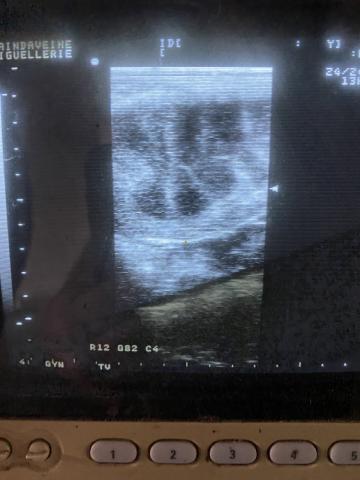

Utérus normal de jument en début d'oestrus

Le vétérinaire prête attention à plusieurs organes lors du suivi gynécologique de la jument, notamment :

• Ovaires: pour détecter les signes d'ovulation et s'assurer que les ovaires fonctionnent correctement.

• Uterus: pour vérifier l'absence d'infections et de troubles de la physiologie, afin d'éviter les avortements, les morts fœtales, etc.